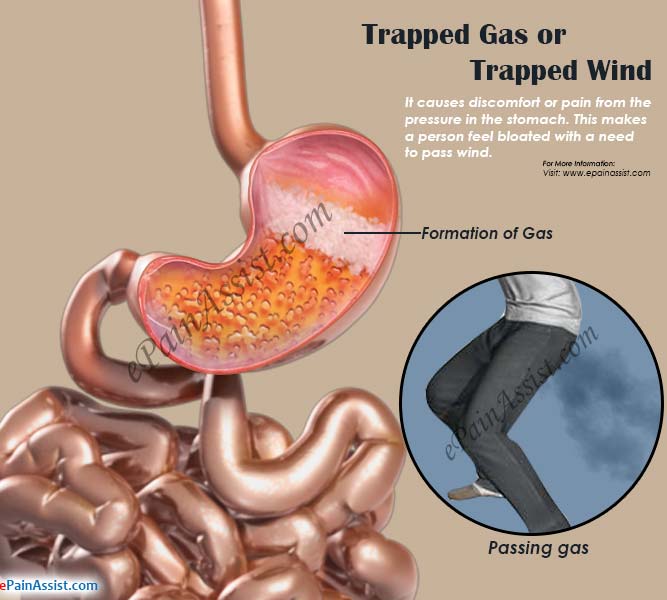

Common Problem – Trapped Gas – Fit Nepal

Pin on Health Tips/Exercise

How To Stop Stomach Gas Pain – Cares Healthy

Pin on Fitness

Pin on Holistic & Spiritual Health

Gas and bloating is an inflammation of the lining of the stomach.The …